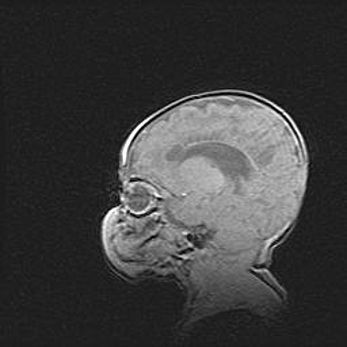

Неполная лизэнцефалия (пахигирия). Открытая гидроцефалия.

Возраст: 17 дней

Вес: 3110 г

Пол: мужской

Окружность головы: 33,5 см

Срок гестации: 35-36 недель

Лизэнцефалия—недоразвитие корковой пластинки и мозговых извилин в результате нарушения миграции нейронов коры. Поверхность мозговых полушарий гладкая. Микроскопически выявляется отсутствие нормальных слоев коры и скопление групп нейронов в подкорковом белом веществе.

Пахигирия—уменьшение числа вторичных извилин. В пораженном полушарии нервные клетки образуют толстый недифференцированный слой с неправильно расположенными нервными волокнами и группами гетеротопных клеток. Нервные клетки незрелые. Белое вещество истончено. При этом нередко аномально развит корково-спинномозговой путь.